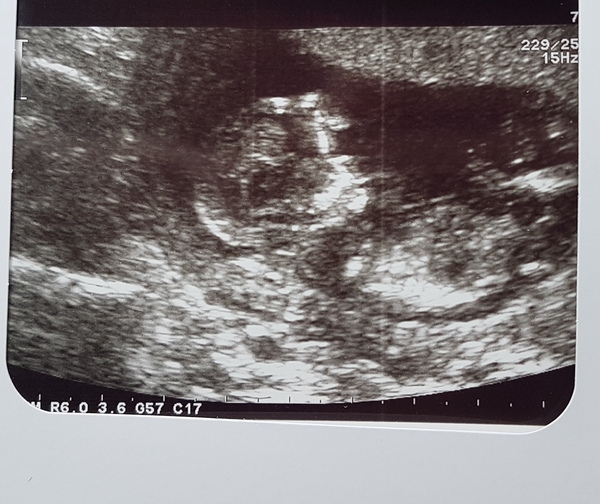

Well that was a palava! Took 2 hours to get to the hospital in the snow. Virtually everyone had cancelled so we were allowed to be late (we left 90mins early!!) Baby wouldn't behave so got sent off for 3 20 min walks 😂 but eventually got the measurements done. Dates brought forward and am now 12+5 due 7th September. I'll join Facebook now!

Yay @Namechangedtoscream look at that lovely baby you're growing 😍

Oh NameChanged look at those little cheeks! You've made it to the 12 week scan!!! You finally made it!!

Excellent scan pic @Namechangedtoscream !

Lovely pic @Namechangedtoscream